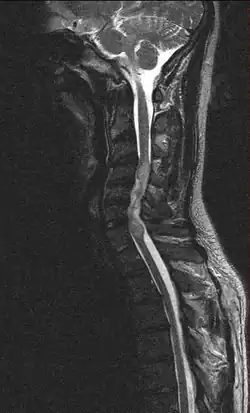

| Ependymoma of the cervical spine, completely obscurating the spinal canal |

Froin's syndrome is the coexistence of xanthochromia, high protein level and marked coagulation of cerebrospinal fluid (CSF). It is caused by meningeal irritation (e.g. during spinal meningitis) and CSF flow blockage by tumour mass or abscess.[1] Stagnation of the CSF within the thecal sac facilitates exudation from the tumour itself and activation of coagulation factors. A clinical test formerly used for evaluation of spinal stenosis is Queckenstedt's maneuver. Nowadays, a magnetic resonance imaging is used for identification of CSF flow obstruction. It often shows the prolongation of T1 and T2 signal in CSF caudal to a level of block.[2] This phenomenon is named after Georges Froin (1874–1932), a French physician who first described it.[3][4]